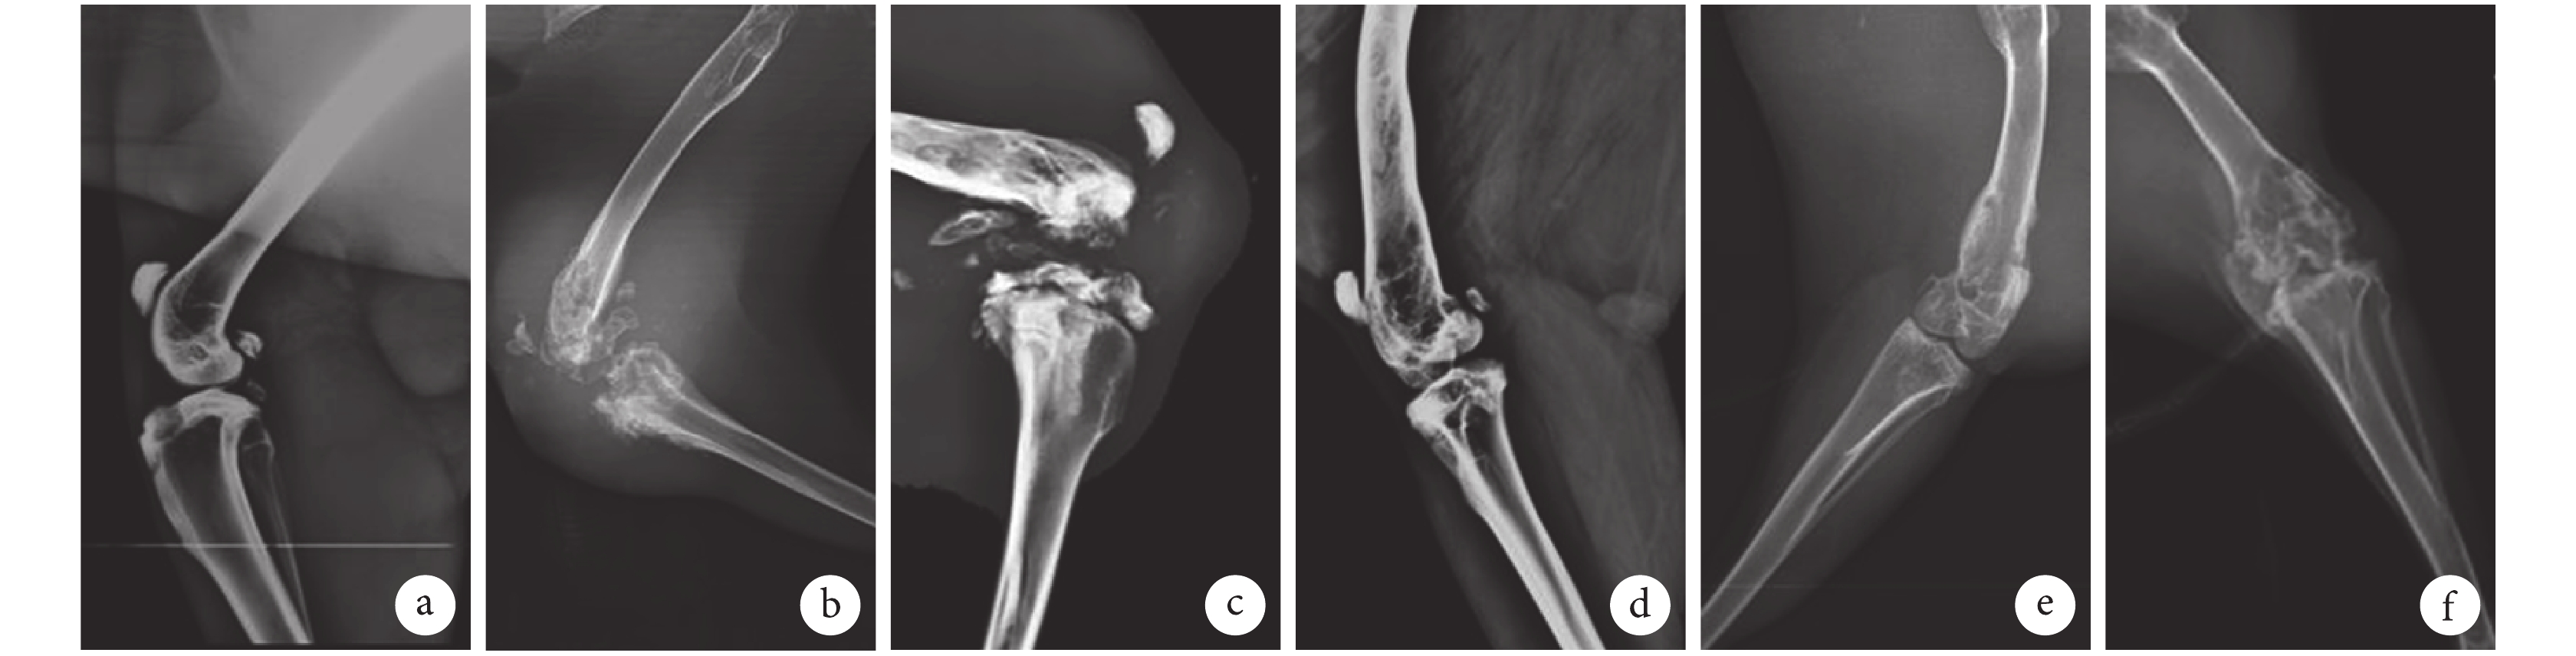

X 線片示:A 組軟組織無腫脹,骨質無破壞,無死骨形成。B~F 組均見不同程度骨質破壞,死骨形成,其中 B 組軟組織腫脹明顯,侵犯至關節;C 組中 2 只侵犯至關節,但侵犯程度不及 B 組;D、E 組均可見死骨形成,股骨破壞腫脹,腫脹程度不及 B 組;F 組可見骨質破壞,骨質增生,破壞程度不及 D、E 組。見圖 2。

A、B、C、D、E、F 組 Norden 評分分別為 0、(6.50±0.86)、(5.92±0.86)、(5.12±0.69)、(4.75±0.80)、(3.69±0.26)分。B~F 組評分顯著高于 A 組,B、C 組顯著高于 D、E、F 組,D、E 組顯著高于 F 組,差異均有統計學意義(P<0.05);B、C 組間及 D、E 組間比較差異無統計學意義(P>0.05)。